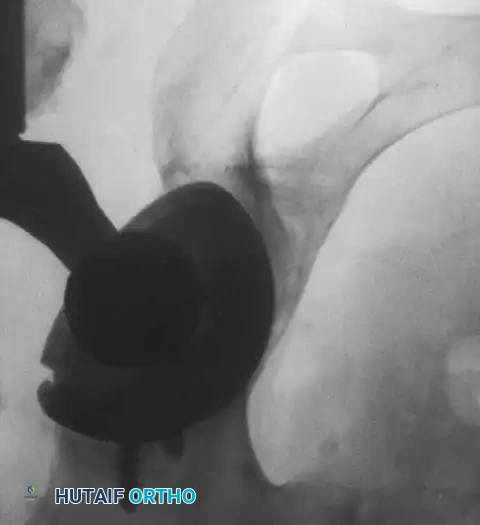

Acetabular Extraction

Removal of a well-fixed cementless acetabular component can result in catastrophic bone loss if not performed meticulously. The use of curved, flexible osteotomes (e.g., the Explant system) allows the surgeon to cut the bone-implant interface precisely along the hemisphere of the cup, preserving the critical subchondral bone of the acetabular dome and columns.

Acetabular Reconstruction

The goal of acetabular revision is to restore the anatomic center of rotation, achieve rigid initial fixation, and provide a biologic environment for long-term stability. Defects are classified using the Paprosky system.

- Type I & II Defects (Cavitary): Managed with hemispherical, highly porous-coated "jumbo" cups (typically >62 mm) and particulate cancellous autograft/allograft. Multiple screws are utilized in the safe zone (posterosuperior quadrant) to achieve rigid primary fixation.

- Type III Defects (Segmental/Severe): Require advanced techniques. Trabecular metal augments are used to fill superior segmental defects and support the cup. In cases of pelvic discontinuity, a cup-cage construct or custom triflange acetabular component may be necessary.